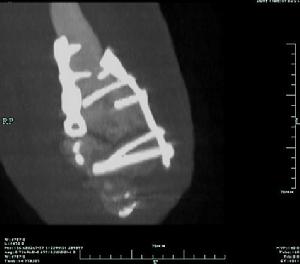

3、X線檢查

除正、側位X線攝片外,尚應根據傷情拍攝特殊體位相,如開口位(上頸椎損傷)、動力性側位(頸椎)、軸位(舟狀骨、跟骨等)和切線位(髕骨)等。複雜的骨盆骨折或疑有椎管內骨折者,尚應酌情行體層片或CT檢查。

無移位者用上肢石膏或石膏托功能位固定,有移位者經復位後達到或近於解剖復位者,

![]() | ![]() |